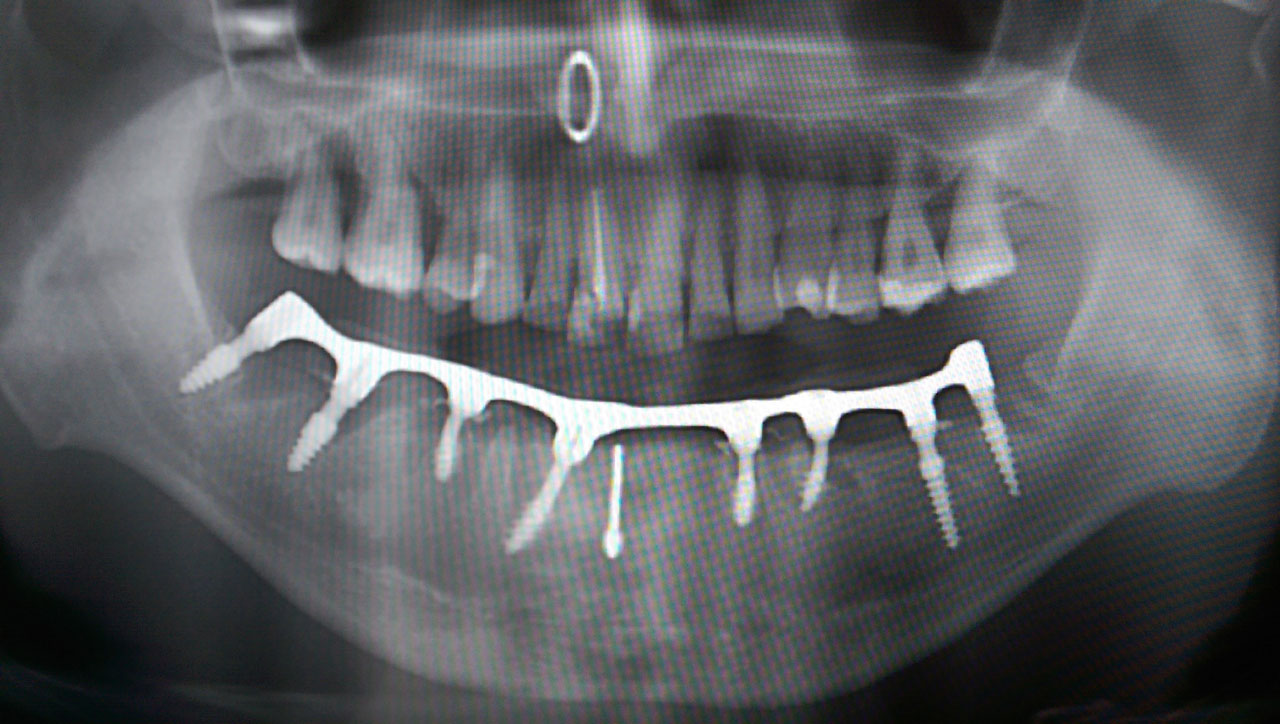

Alsó állcsont teljes rehabilitációja 72 óra alatt, azonnal terhelhető implantátumokkal súlyos paradontitisben szenvedő dohányzó páciens esetében. Az alsó állcsont fogai mind mozogtak az előrehaladott fogágypusztulás miatt.

A fogakat eltávolítottuk, a gyulladt, fertőzött csontot kitakarítottuk, kifertőtlenítettük, majd azonnal implantáltunk.

Svájci, IHDE márkájú, azonnal terhelhető implantátumokat helyzetünk be, és ezekre harmadnapra rögzített, hosszútávú, fémvázas, esztétikus műanyaggal leplezett hidat ragasztottunk be.

Ezt az ideiglenes hidat a sebek gyógyulása miatt használjuk, de tartóssága miatt véglegesként is használható. A legtöbb esetben, ahogy itt is, 6 hónap múlva porcelán hídra cseréljük, a teljes gyógyulás után.